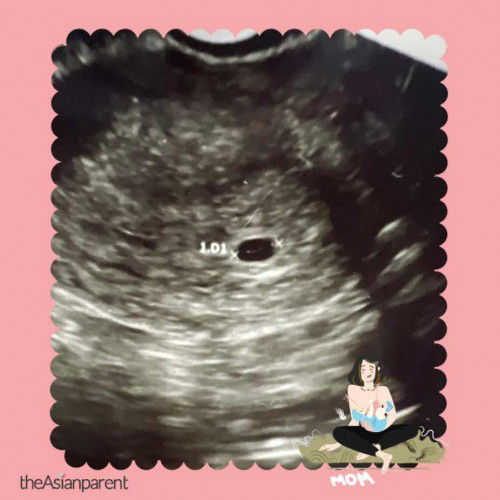

hi mumy2 , normalkah bila scan dari perut tak nampak kantung ,tapi bila scan dari bawah baru nampak kantung itu pun size kantung 0.73cm kata doktor size ini lebih kurang 4minggu ,tapi ikt calendar cycle period 6minggu 6 hari ..? tapi stiap bulan memng cycle period saya 40 hari ? ada bumil yang lain perna alami hal yang sama? sebb takut seblum perna keguguran